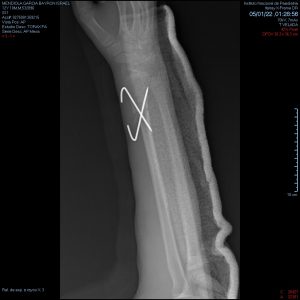

- Fracturas de antebrazo

- Fractura de radio y cubito

Fractura radiocubital

Fractura de radio distal